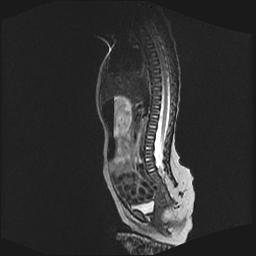

四个月的女婴,ct示脊膜膨出.

脂肪脊髓脊膜膨出

脊柱裂、脊膜膨出